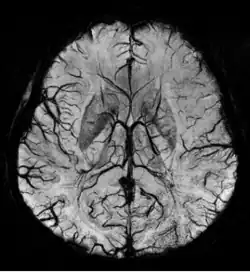

Susceptibility weighted imaging (SWI), originally called BOLD venographic imaging, is an MRI sequence that is exquisitely sensitive to venous blood, hemorrhage and iron storage. SWI uses a fully flow compensated, long echo, gradient recalled echo (GRE) pulse sequence to acquire images. This method exploits the susceptibility differences between tissues and uses the phase image to detect these differences. The magnitude and phase data are combined to produce an enhanced contrast magnitude image. The imaging of venous blood with SWI is a blood-oxygen-level dependent (BOLD) technique which is why it was (and is sometimes still) referred to as BOLD venography. Due to its sensitivity to venous blood SWI is commonly used in traumatic brain injuries (TBI) and for high resolution brain venographies but has many other clinical applications. SWI is offered as a clinical package by Philips and Siemens but can be run on any manufacturer's machine at field strengths of 1.0 T, 1.5 T, 3.0 T and higher.